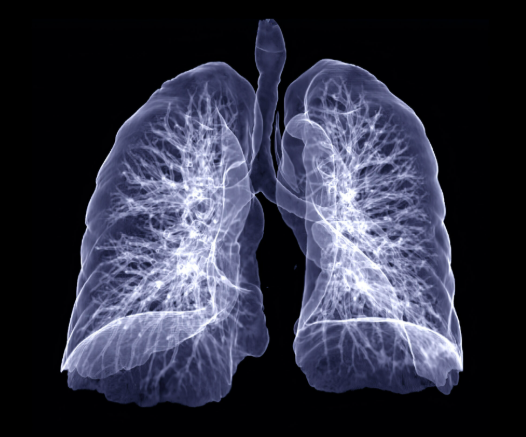

폐결절이란? 정의와 기본 정보

폐결절은 폐 안에 생긴 3cm 이하의 고형성 음영 또는 병변을 말합니다. 일반적으로 건강검진에서 시행하는 흉부 X-ray에서는 발견되지 않는 경우가 많으며, CT 검사에서 우연히 발견되는 경우가 많습니다.

결절의 모양은 다양할 수 있으며, 일부는 과거 감염, 섬유화, 염증의 흔적일 수 있습니다. 문제는 이러한 결절이 폐암 초기일 가능성도 있기 때문에, 무조건 안심할 수 없다는 데 있습니다.

하지만 많은 연구에서 폐결절의 상당수가 양성으로 확인되며, 전체 결절 중 악성일 확률은 5~10% 정도라고 알려져 있습니다. 그러므로 폐결절이 곧 폐암이라는 공포로 이어질 필요는 없습니다.